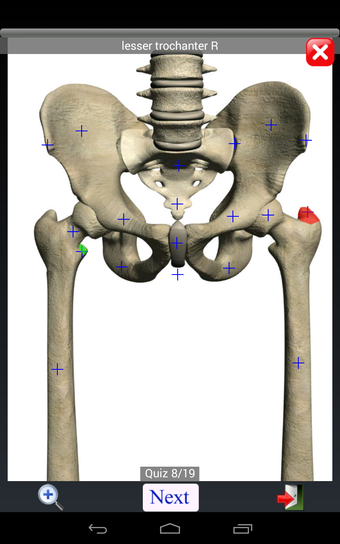

Anatomy Quiz Free es una aplicación de Android de Education Mobile que ofrece una amplia gama de cuestionarios para ayudar a los usuarios a aprender anatomía humana. La aplicación cuenta con más de 500 cuestionarios que ponen a prueba tu capacidad para identificar la ubicación correcta de un objeto dado su nombre. Los cuestionarios se generan a partir de modelos de anatomía 3D virtuales, lo que los hace más atractivos e interactivos. La aplicación es gratuita y no hay versiones premium ni compras dentro de la aplicación.

La aplicación es compatible con los idiomas inglés, francés, español y alemán, lo que la hace accesible para usuarios de diferentes partes del mundo. Las imágenes de alta resolución son nítidas y claras, y la función de zoom con pellizco te permite acercar y alejar las imágenes para una mejor vista. El cuestionario de posición viene con un temporizador, lo que lo hace más desafiante y emocionante. Además, la aplicación tiene una función de transferencia a la tarjeta SD, lo que facilita su transferencia a otros dispositivos.